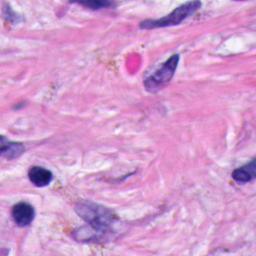

All the digital pathological images included are captured as WSIs using the Huron TissueScope LE1.2 [44]. The scanner automatically digitizes, processes and stores the images of tissue slides in .tif format. To create a database with high diversity, the tissue slides used are cut from 9 distinct types of organs (i.e. 9 Slides). When scanning through a whole organ tissue slide, the scanner captures multiple image patches all in one, which are called Strips. We include 2 strips for each tissue slide to ensure we take different morphological structure across a wide tissue area. The WSI scanner generates several in-depth Z-stacks for each strip, where each z-stack is referred as a Slice. Different z-stacks represent different vertical positions of the WSI camera, which is highly related to the image blur. We include 16 z-stacks for every image strip of a certain tissue slide in the pathology database. In addition, we randomly choose 3 different positions and accordingly crop 3 image patches of from the raw image captured by the whole slide imaging system. To summarize, the total number of images included is , cropped from . The database is called FocusPath and is publicly published in 222FocusPath database https://sites.google.com/view/focuspathuoft. A sample of 16 different focus levels is shown in Figure 5. Note that we have an extended version of FocusPath containing images extracted from positions instead of for ISA analysis. Since the database is too big, we avoid uploading it online, but it can be requested from the authors on demand.

To generate a “subjective-like” score for FocusPath database, we assigned a “focus level” for each image that is determined by the difference between the best camera position and the position of interest . In other words, the score represents how far the camera is away from its best focus level when scanning a certain image slide. Specifically, every 16 images of the same content but different blur levels have a common and every image has a corresponding . A sample set of 16 images is shown in Figure 5. The value among every 16 images is determined by the proposed non-reference sharpness assessment metric in this paper. Since is found among 16 different slices of the same tissue content, the scores will guarantee to obtain the best focus level. The plot of focus level scores across 16 images is shown in Figure 6. The mathematical representation of the focus level for sharpness scoring is defined by

To make it clearer, we list the relevant information about the FocusPath in Table III. In addition, as mentioned before, we include 9 tissue slides in FocusPath. They are from different types of organs with different staining types, which guarantees diversity and effectiveness of the database. Further information about the tissue slides and sample images are available in Table II.